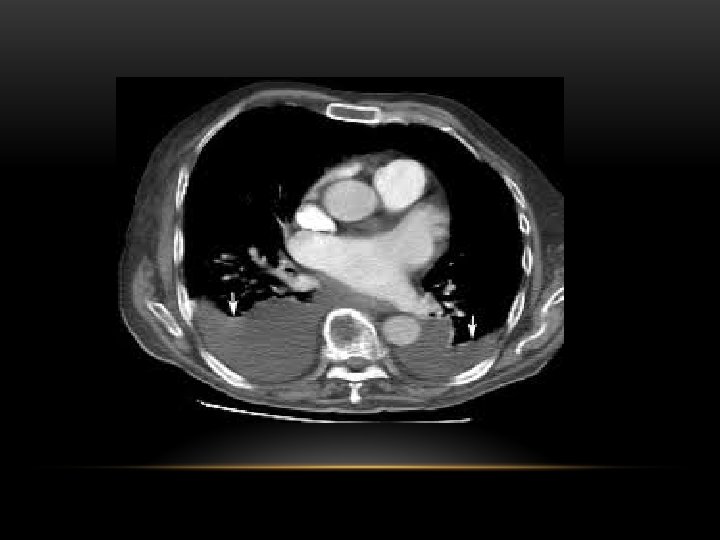

CT scan of left empyema with pleural enhancement